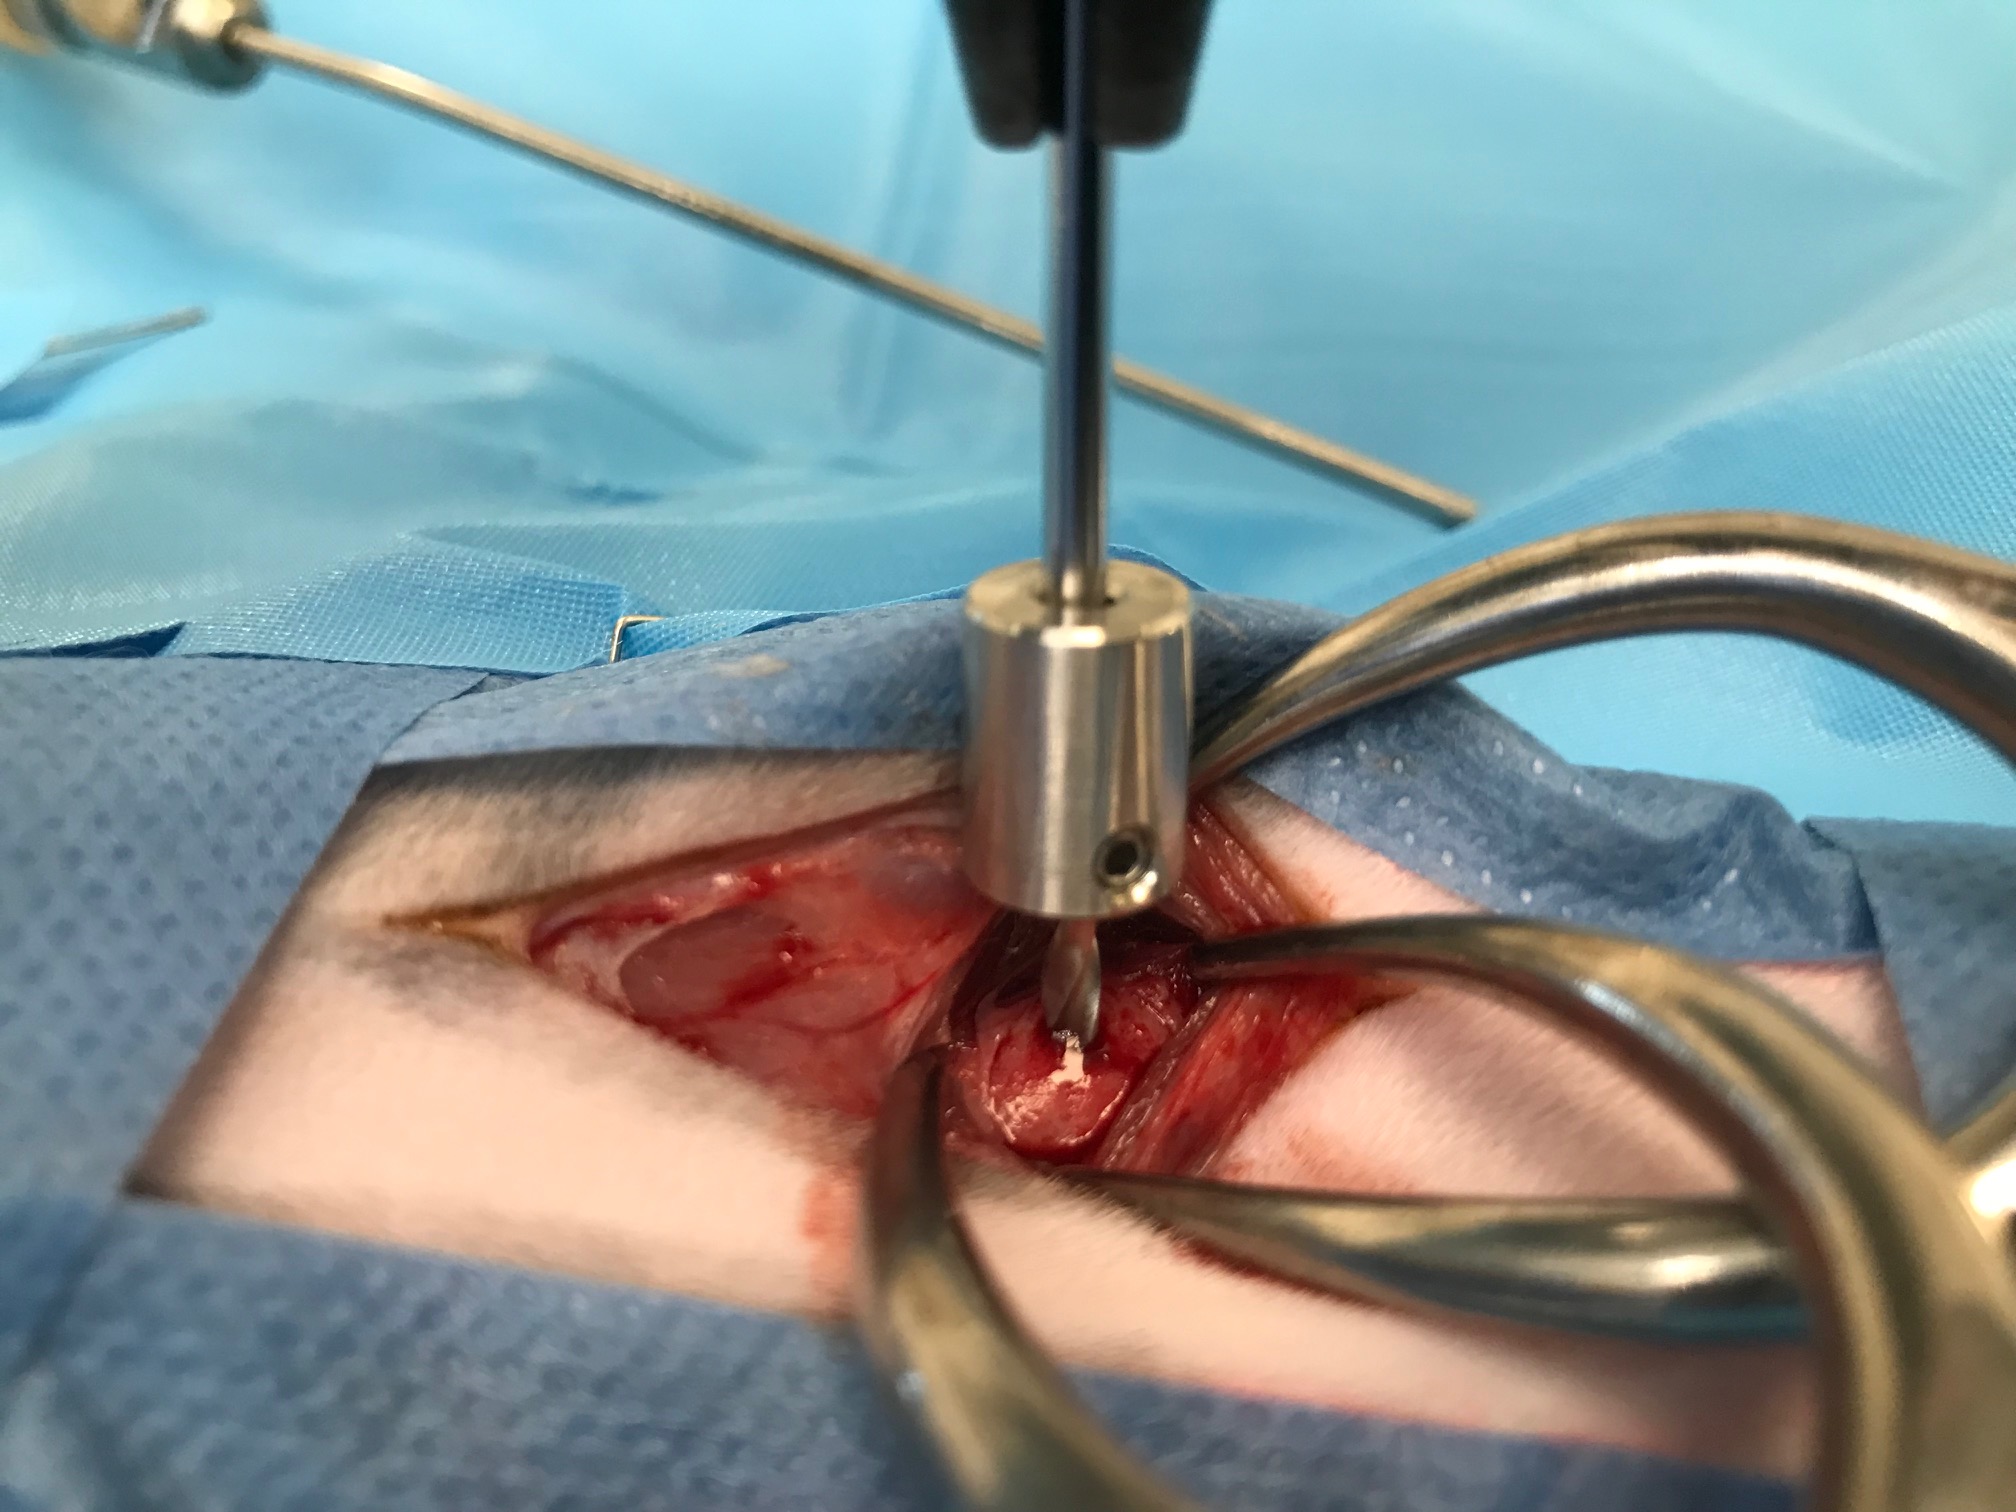

-Les étapes de la TECALBO en photos et vidéos

TECALBO : comment la réaliser en pratique.